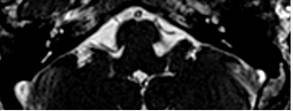

Se realizó una resonancia magnética nuclear (RMN) de oído interno mediante la que se observó un asa vascular en el ángulo pontocerebeloso izquierdo que ingresaba al conducto auditivo interno (CAI) en menos de 50 % de su longitud. Clasificación anatómica Chavda tipo II, formando un bucle entre el complejo del VII-VIII par craneal. (Fig. 1 y Fig. 2).

La introducción de la resonancia magnética nuclear (RMN) ha permitido visualizar adecuadamente el APC, siendo el método de elección para la evaluación del VII-VIII par craneal en pacientes con síntomas vestibulares y auditivos. 10,11 Es el método no invasivo más apropiado para la evaluación de la estructura microvascular en esa región. 12